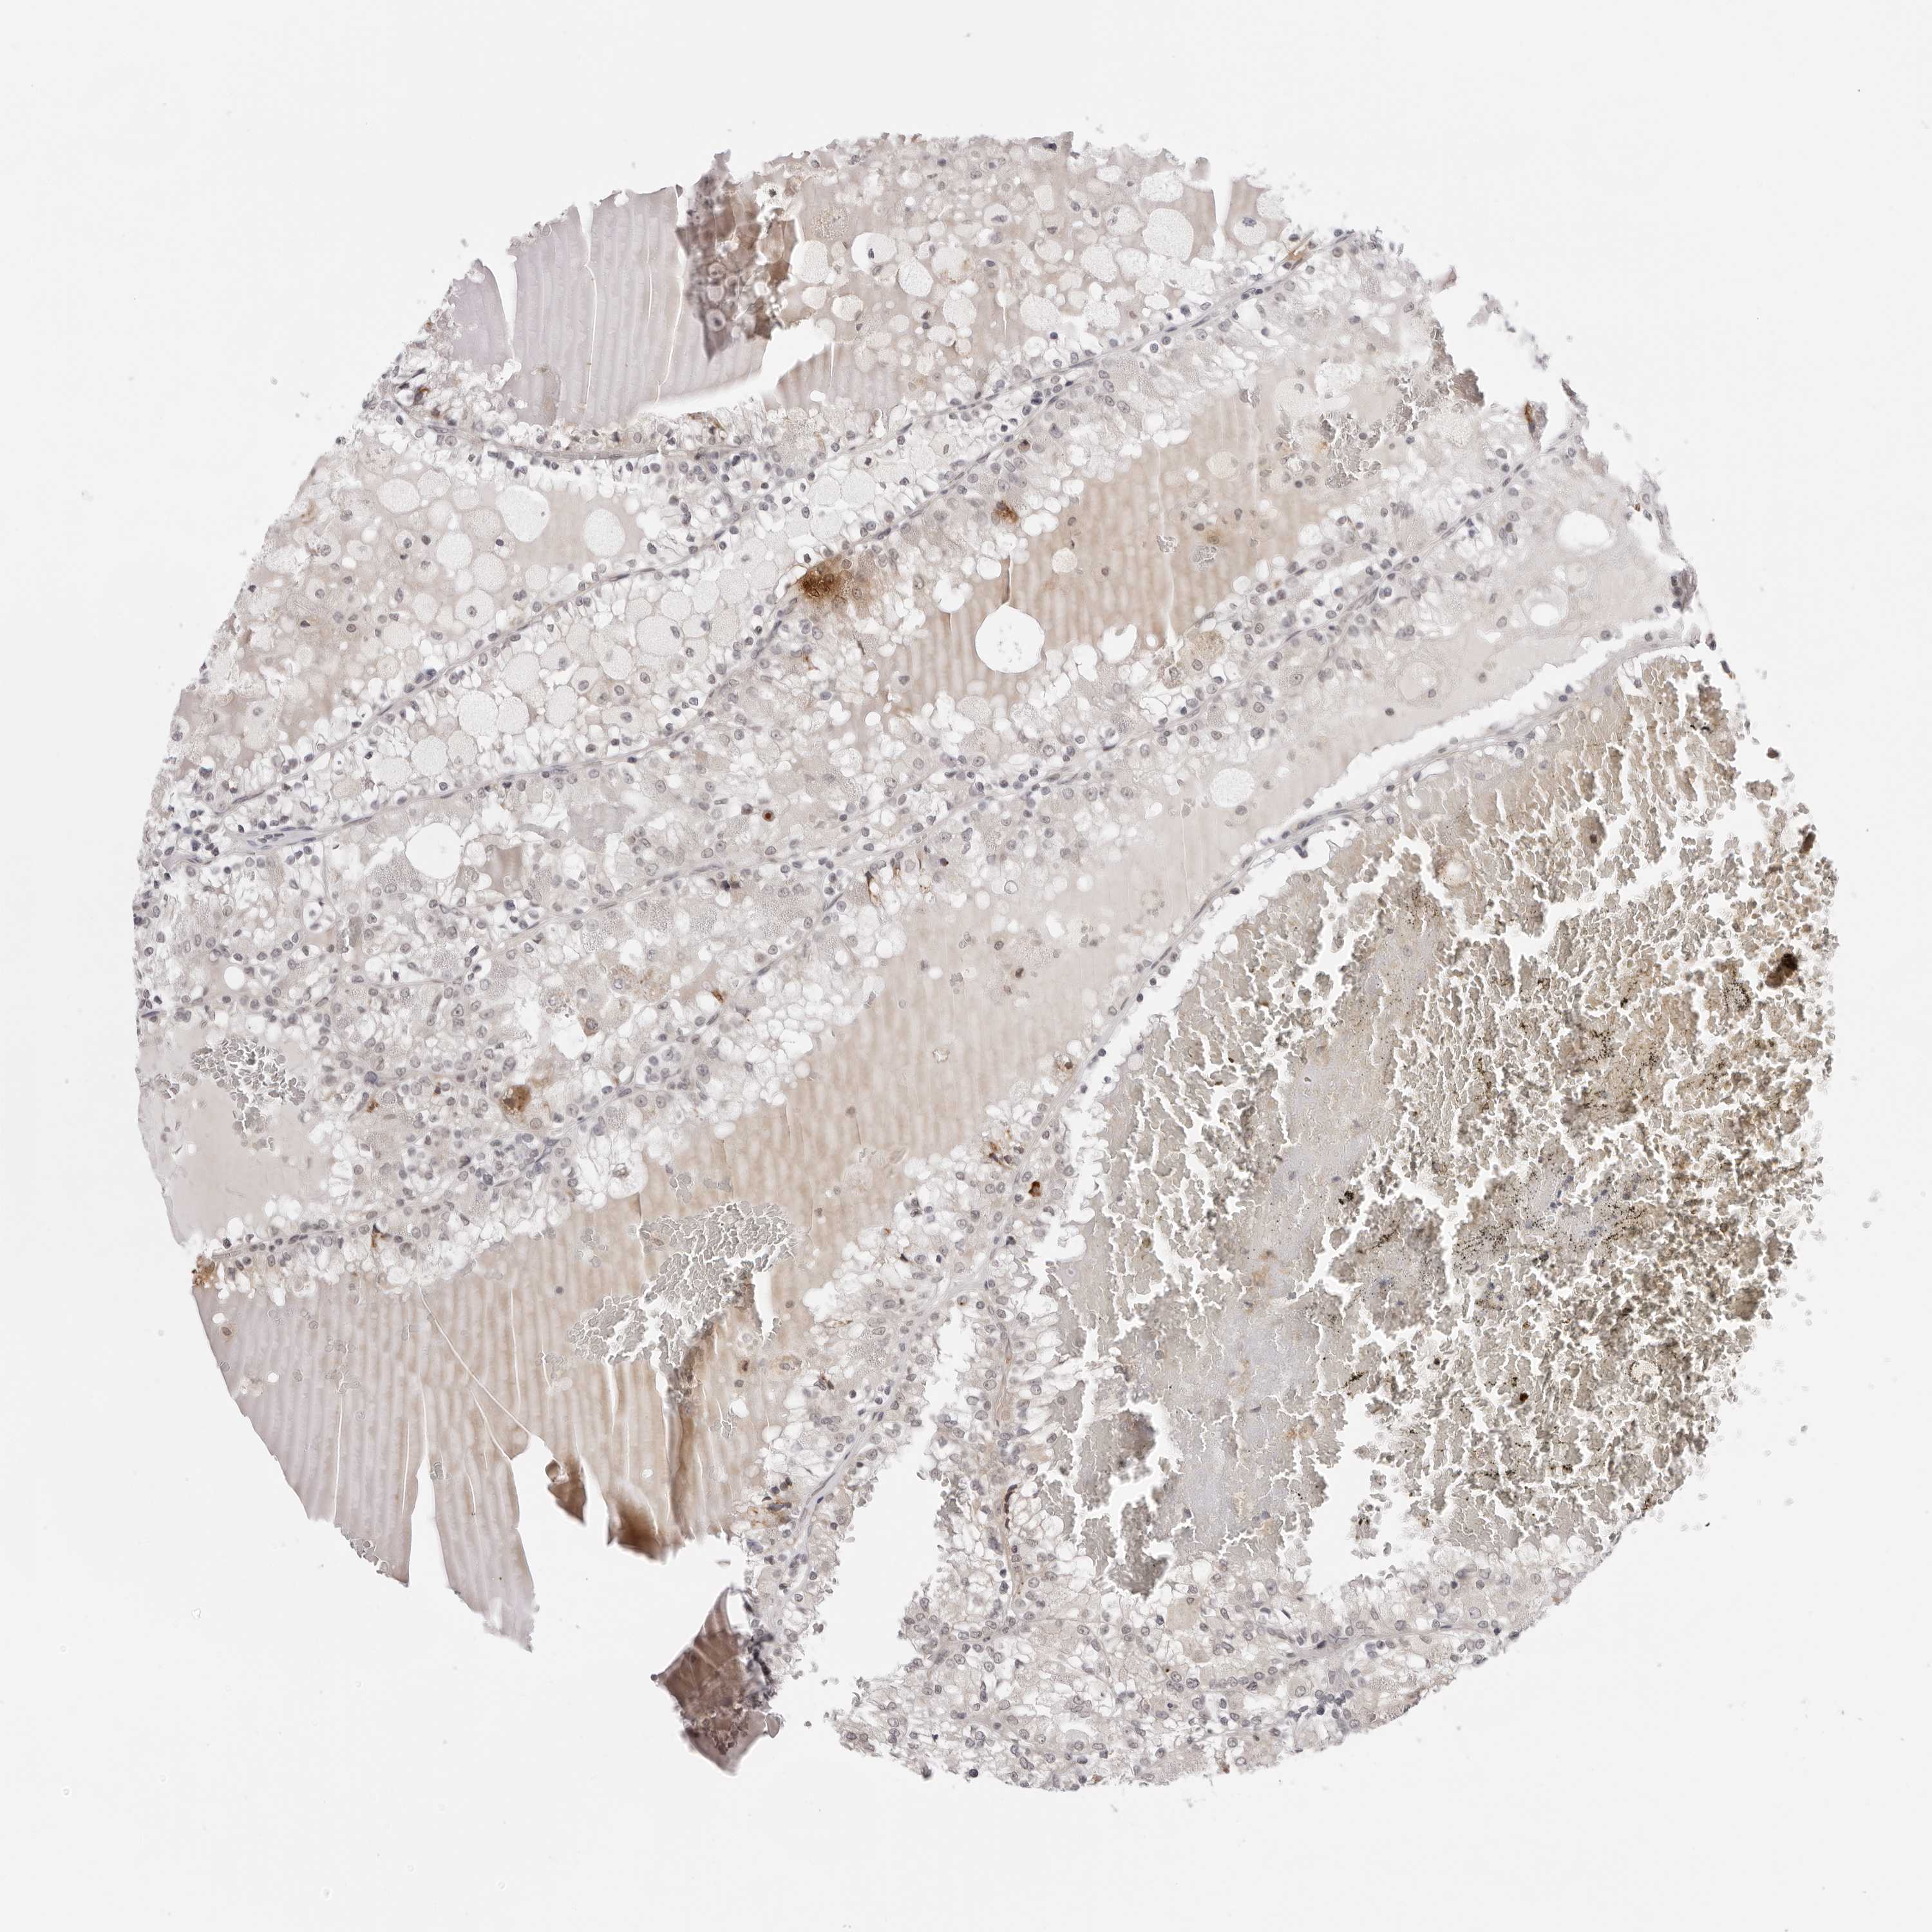

CANCER RENAL CANCER Show tissue menu

KICH TCGA KIRC TCGA KIRC VALIDATION KIRP TCGA PROTEIN RCC CPTAC PROTEIN EXPRESSION